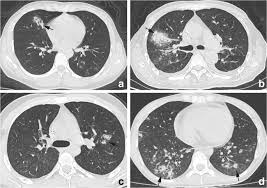

Entropy Free Full Text Classification Of Covid 19 Coronavirus Pneumonia And Healthy Lungs In Ct Scans Using Q Deformed Entropy And Deep Learning Features Html

Entropy Free Full Text Classification Of Covid 19 Coronavirus Pneumonia And Healthy Lungs In Ct Scans Using Q Deformed Entropy And Deep Learning Features Html from www.mdpi.com

Black Hole In The Lung Bone Marrow Transplantation

Black Hole In The Lung Bone Marrow Transplantation from media.springernature.com

A Classification Of Pulmonary Nodules By Ct Scan Ecancer

A Classification Of Pulmonary Nodules By Ct Scan Ecancer from ecancer.org